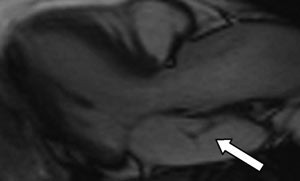

Pasienten ble også utredet med magnetisk resonanstomografi (MR) (fig 5) med tanke på sammenlikning med de ekkokardiografiske metodene. Undersøkelsen viste normale dimensjoner og funksjon i alle kamre, og var dermed i overensstemmelse med ultralydundersøkelsene.

MR gir også svært gode bilder av strukturer i hjertet. Måling av blodstrømshastigheter, slik som ved dopplerultralyd, er også mulig ved MR. MR gir også bedre romlig oppløselighet enn de ekkokardiografiske metodene. Ulempene med MR i forhold til ekkokardiografi er i første rekke dårligere tilgjengelighet, både når det gjelder apparatur og kompetent personale. Dessuten er MR-undersøkelsene tidkrevende og kan være problematisk hos pasienter med arytmier eller hyppige ekstrasystoler.